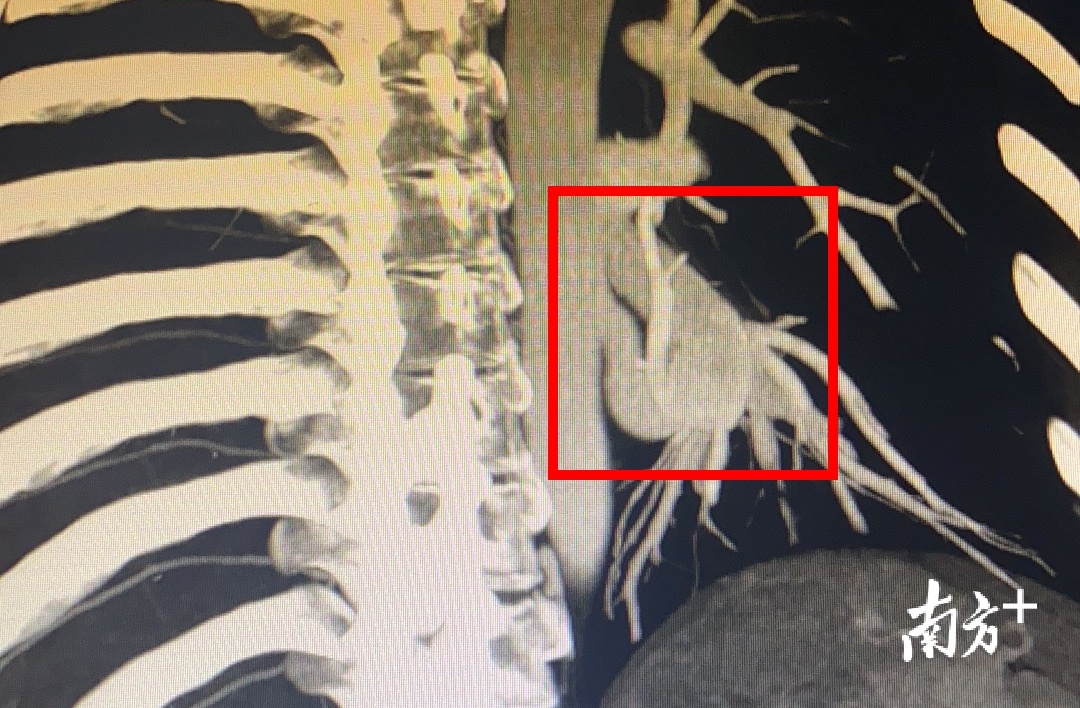

不久前,30多岁的珠海王女士反复咯血一个星期,随后到中大五院就诊检查发现左肺部有一肿块,大小占整个肺部的三分之一,看上去如同“多了一个肺”,胸部增强CT明确诊断为肺隔离症伴肺内出血。

中大五院外科主任、胸外科主任曹庆东教授介绍,正常人有左右2个肺,通常左肺有2片肺叶,右肺有3片。该患者在左侧肺又多长了1片肺叶,通俗来说就是长了“3个肺”,但“第3个肺”的动脉不与正常的肺动脉相连,却连着胸主动脉,支气管也发育不正常。

该患者出现了反复咯血,同时肺内发生血肿,左下肺已几乎没有功能。曹庆东教授手术团队急诊行单孔胸腔镜下左肺下叶切除术,术中发现该患者降主动脉的异常血管“比拇指还要粗”。这场微创术用时50分钟出血量仅10毫升。术后第一天患者便可下地活动,目前她恢复良好,已顺利出院。